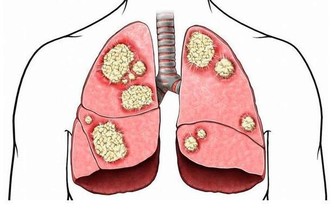

熱衰竭,由高溫引起的相對溫和的健康問題,可以是高溫暴露體液補給不足,或身體水鹽礦物質不平衡,經由幾天的連續積累發展而來。

症狀包括眩暈頭痛、噁心據吐、大量出汗臉色蒼白,體溫稍高或正常、極度虛弱或疲倦、肌肉痙、昏厥等患者如有反、腹瀉或嘔吐,可能會導致熱射病。老年人、血壓患者、在高溫環境中進行重體力勞動或長跑等劇烈運動的人更易發生熱衰竭。

2怎樣處理